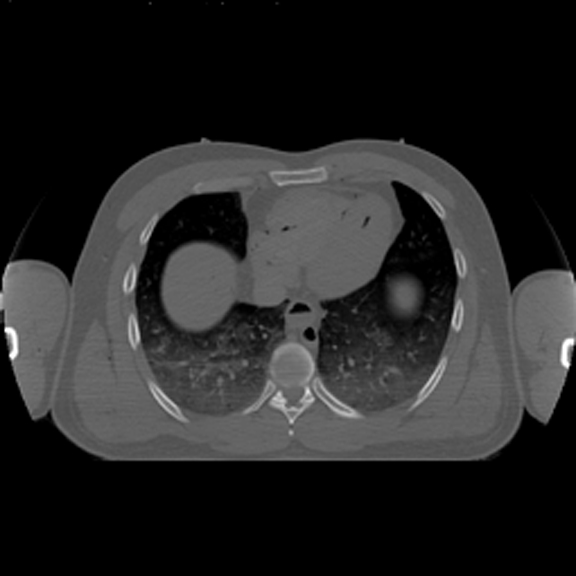

Horizontal CT Section at this level